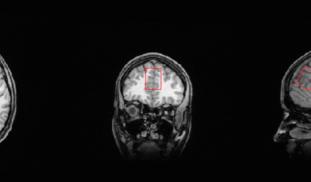

We hypothesize that the administration of two widely available, naturally occurring dietary supplements, in addition to standard antidepressant therapy, will reduce severity of depression in individuals residing at higher altitudes. The Intermountain West is known for depression and suicide rates that are higher than the national average and it is important that we investigate more effective novel treatments for individuals who reside at elevation.